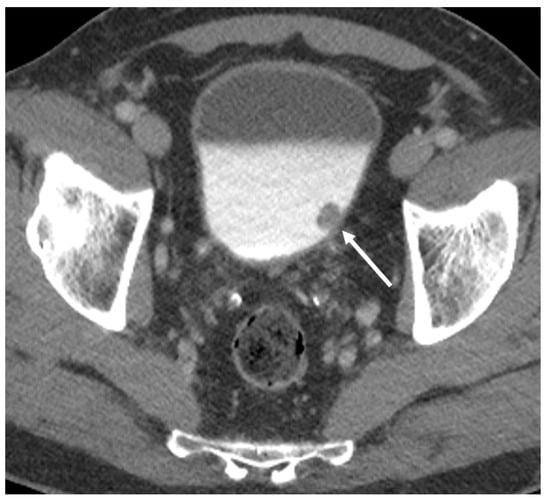

2.2. Staging

2.3. Restaging